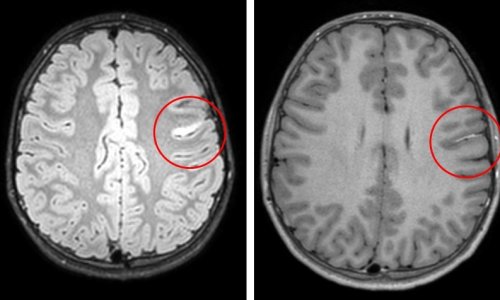

Prof. Sorantin ist nicht nur Radiologe, sondern auch Kinderarzt – und das mit Leidenschaft. Das Wohl des Kindes steht für ihn an oberster Stelle. „Kinder sind keine kleinen Erwachsenen. Es bestehen gravierende Unterschiede, nicht nur im Hinblick auf die Größe, sondern auch auf Proportionen und „Body Composition“, zum Beispiel der Verkalkungsgrad. Diese Parameter müssen in Belichtungsprotokolle, in Expositionsparameter und auch in MRT-Sequenzen umgesetzt werden.“ Dabei umfasst die Kinderradiologie vom Fötus bis zum Adoleszenten alle Körperregionen, von Kopf bis Fuß, mit allen Modalitäten – und sie muss eine Fülle von Unterschieden beachten. Kinder und Jugendliche haben ganz andere Pathologien als Erwachsene und auch die Strahlenempfindlichkeit verändert sich im Laufe des Heranwachsens. „Je kleiner das Kind, desto höher ist die Strahlenempfindlichkeit. Insbesondere das Gehirn ist in den ersten Lebensjahren besonders empfindlich, weil es noch nicht verschaltet ist, wohingegen die Geschlechtsorgane erst ab dem Jugendalter eine höhere Strahlenempfindlichkeit entwickeln“, erläutert der Kinderradiologe. Umgekehrt kommt den Radiologen die kindliche Entwicklung aber auch zu Hilfe. Wegen der schwächeren Verkalkung der Knochen und anderer Körperproportionen kann der Ultraschall besser genutzt werden. „Der Radiologe sollte alle diese Dinge berücksichtigen: Er sollte nicht nur das richtige Verfahren wählen, sondern dieses Verfahren auch für das Kind optimieren können.“

Die Praxis sieht mitunter aber anders aus. Eine Befragung der Internationalen Atomenergie-Behörde (IAEO) im Jahr 2012 hat ergeben, dass bei etwa 13 Prozent der CT-Untersuchungen von Kindern die Dosis überhaupt nicht verändert wird und dass sich in über 40 Prozent die Untersucher gemäß der Firmenprotokolle verhalten. „Bei deutlich der Hälfte der Patienten ist damit die Dosis nicht adäquat. Das ist 100 Jahre nach dem ALARA-Prinzip schon deprimierend“, so Prof. Sorantin. Wenn die Dosis nicht an die Kinder adaptiert wird, hat das gravierende Folgen. Laut einer australischen Studie von 2013 verursacht jede dritte bis vierte Schädel-CT im Kindesalter eine Leukämie oder einen Hirntumor im weiteren Lebensverlauf, bei einem Body-Scan treten bei etwa jedem achten bis neunten Kind schwerwiegende Strahlenspätfolgen auf.